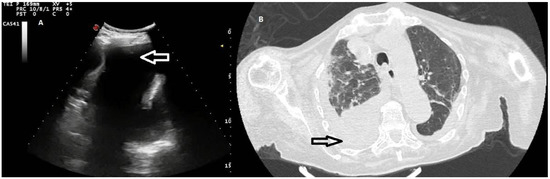

Figure 4. (A) TUS scan showing a homogeneous iperechoic pleural exudates viewed by a convex multifrequency probe (3.5 MHz). The drained fluid was macroscopically hemorrhagic. (B) The corresponding CT scan shows a large right effusion in a patient with a diagnosis of metastatic kidney cancer.

Twenty out of 22 homogeneous hyperechoic effusions (90.91%) were macroscopically hemorrhagic (Figure 4).